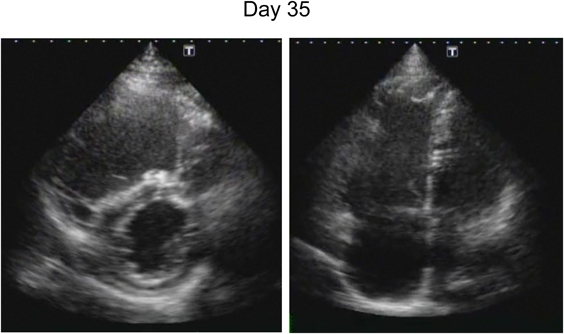

ダビガトランで右室内血栓が消失した不整脈原性右室心筋症の1例Dissolution of a Right Ventricular Thrombus with Dabigatran Etexilate in Arrhythmogenic Right Ventricular Cardiomyopathy